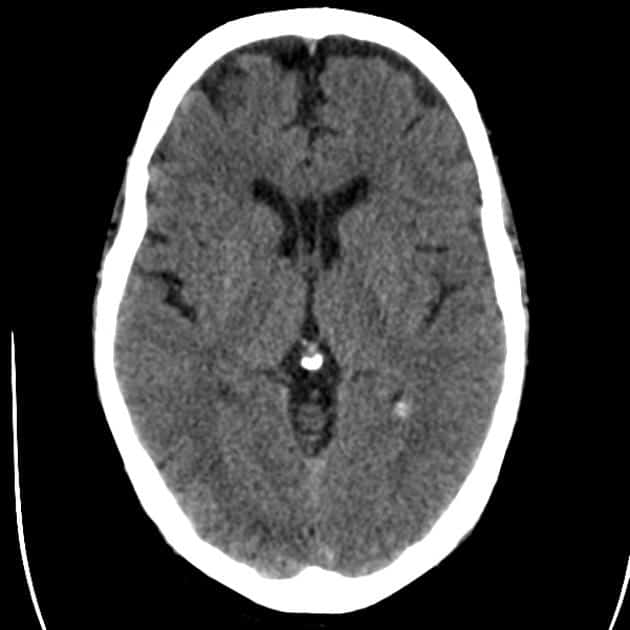

Nang vách trong suốt

Nang vách trong suốt - Ảnh 3

» Thông tin: Nam giới – 50 tuổi.

» Lâm sàng: Kiểm tra sức khỏe.